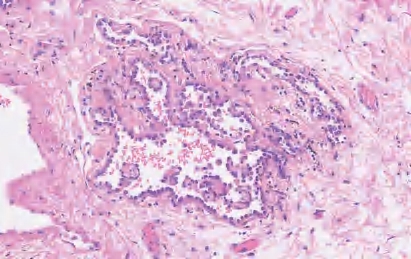

(2)腺泡型腺癌:主要成分是由恶性上皮细胞围成的圆形、椭圆形的腺泡或管腔状结构(图2-4),此类型腺癌的腺腔内和肿瘤细胞内可有黏液。有时沿着肺泡壁生长会出现折叠,形成内陷的腺样细胞巢,很难与腺泡生长方式(浸润性生长)相鉴别。鉴别要点:①腺泡型腺癌肿瘤细胞周围肺间质有肌纤维母细胞反应;②肺泡原有结构消失。大的腺泡内出现的由多个背靠背的小腺腔构成的癌,称为筛状癌。目前认为筛状癌是腺泡型腺癌的一种生长模式,与预后不良相关。

图2-4 腺泡型腺癌